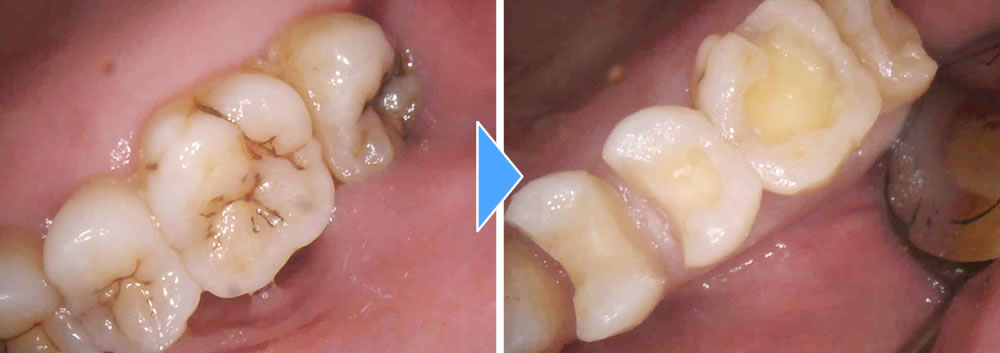

虫歯治療後にセラミックインレーで修復した症例

こちらの患者さまは、検診希望で来院されました。自覚症状はありませんでしたが、レントゲン写真と視診での検査の結果、左上の奥歯4本の歯と歯の間や咬合面に虫歯が確認できました。

虫歯の範囲が大きかったため、部分的なつめ物での治療を提案しました。患者さまの希望で4本とも虫歯の再発リスクが少なく、審美的にも綺麗なセラミックインレーを選択されました。まずは麻酔を行い、虫歯を全部取り切り、神経を保護する処置を行い形を整え、型取りまでを1回の治療で行いました。

セラミックインレーの装着・治療完了

1週間後、完成したセラミックインレー(Emax)をレジンセメントにて合着し、咬み合わせを調整して治療完了となりました。治療後は問題なく噛むことができ、審美的にも機能的にも大変満足していただけました。